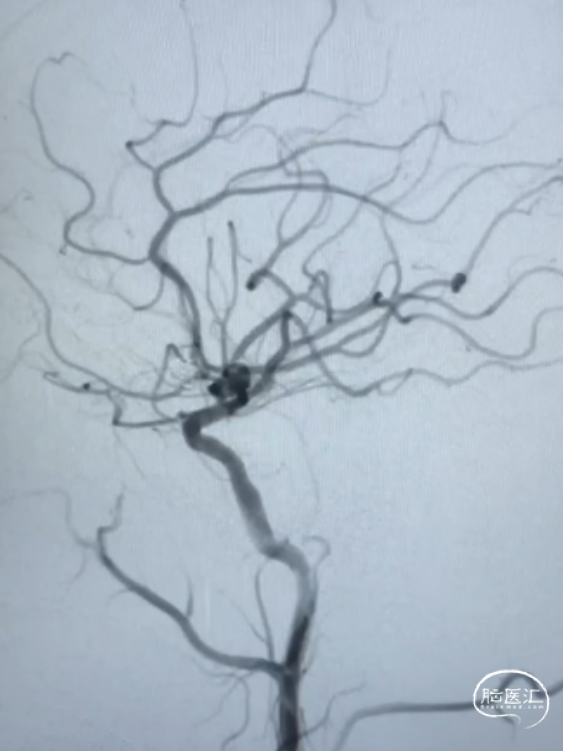

术前影像

左侧大脑中动脉M2段动脉瘤,前交通动脉瘤栓塞术后。

患者取仰卧位,麻醉成功后,行双侧腹股沟处碘伏消毒3遍,铺无菌洞巾,以Seldinger法行右腹股沟股动脉穿刺,置6F动脉鞘,以5F多功能管造影可见左侧大脑中动脉M2段动脉瘤。